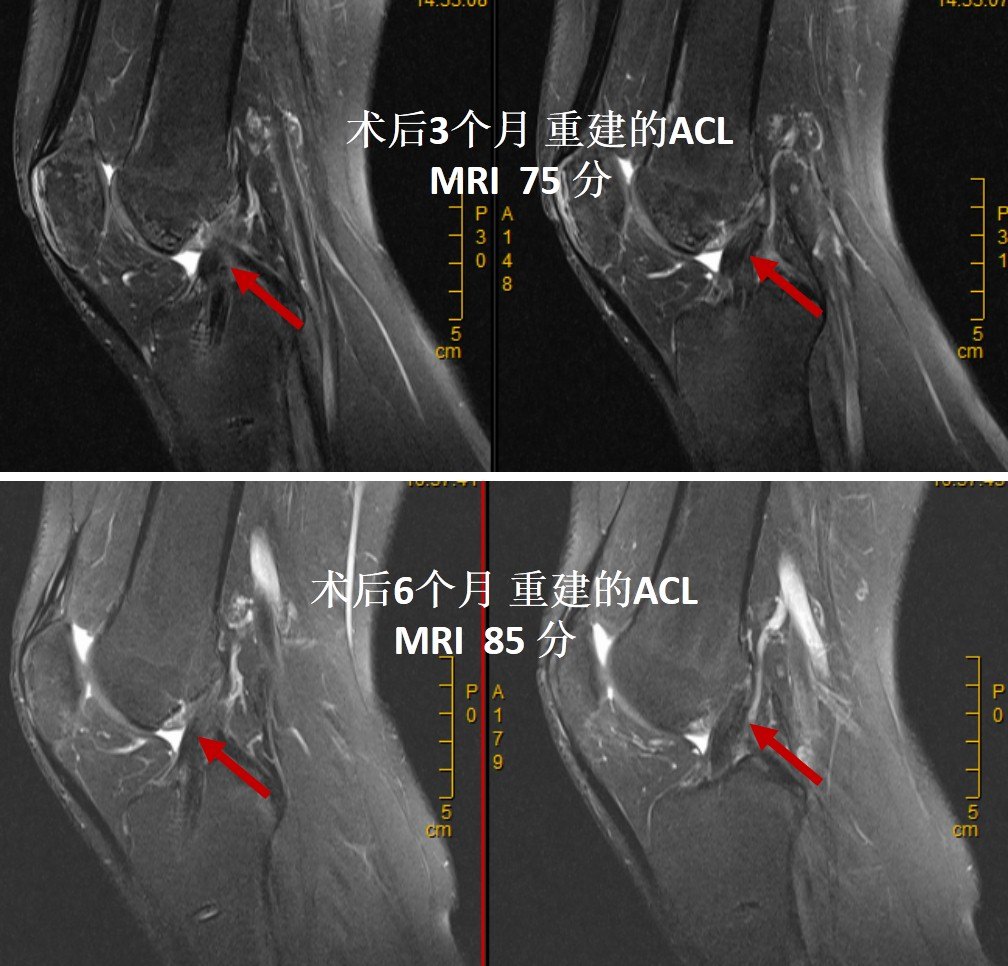

ACL重建后进行MRI评估是评估重建ACL塑形的最直观的非创伤性检查方法。我们的观点认为,如果重建的ACL在MRI上的评分在80分以上(MRI的三个评估指标,总分90分:韧带的容积-30分;韧带的张力-30分;韧带的灰度-30分),术后膝关节功能就恢复好,再次恢复到伤前运动状态的几率就大,重建韧带发生再断裂的风险就低。而且我们在随访过程能根据重建的ACL在MRI上的评分结果调整康复进程,指导患者的运动方法,以利于重建韧带的最终塑形,这个十分重要的。

也有些患者在前交叉韧带重建术后3个月到半年,韧带已经塑形十分完好!